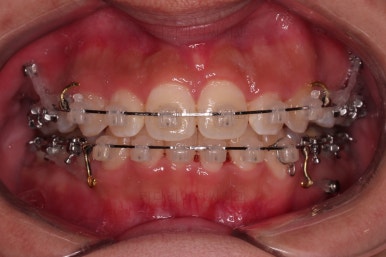

종료 시의 사진들을 전후 비교해 보겠습니다.

입매가 좋아졌고 입을 다무는 편안함도 좋아졌으며 치열이 가지런해졌으며 웃을 때 보이는 치열의 느낌도 좋고 교합도 잘 마무리 되었네요.

지켜봐도 되는 충치는 지켜보기로 여지를 남기고 필요한 충치치료도 마무리를 했습니다.

이상 부산청소년치아교정 키다리아저씨치과에서 시행한 덧니, 돌출입 개선 사례였습니다.